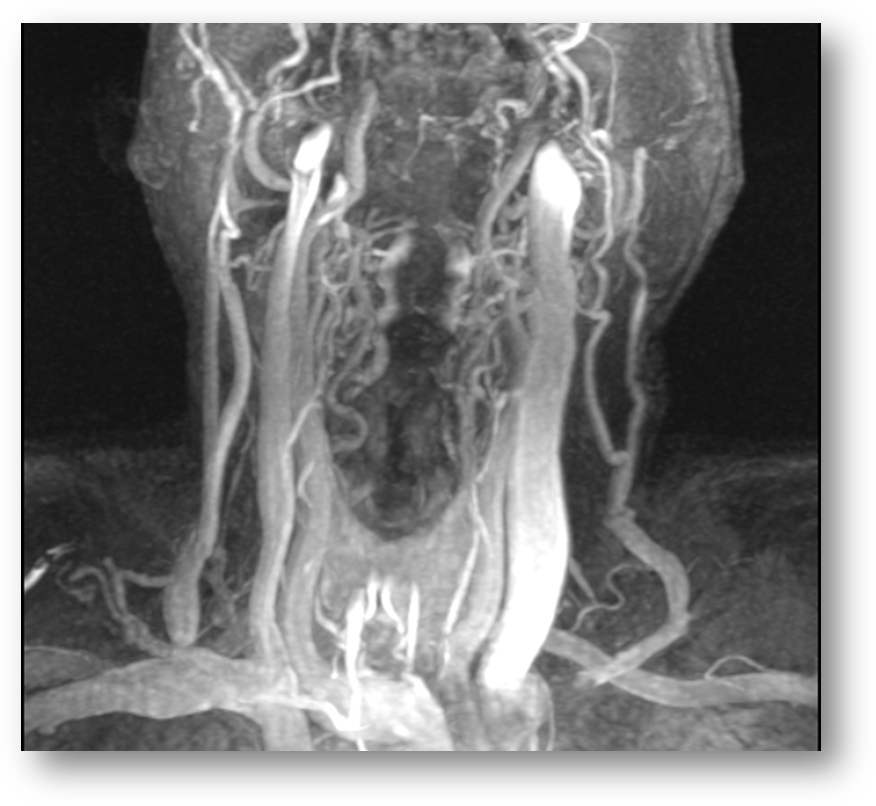

Refer to caption

Figure 7: 3D time-of-flight image of the carotid vasculature. Axial section of neck shown.

MRA is a set of magnetic resonance-based techniques for imaging the circulatory system. Figures (9) and (10) show MRA images of the Circle-of-Willis. MRA techniques can be broadly categorized into flow-dependent and flow-independent groups. The flow-dependent methods derive contrast from the motion of blood in vasculature relative to the static state of surrounding tissue [33]. Two currently well-known and used examples of flow dependent methods are: (i) Phase contrast MRA, (PC MRA) [34, 37, 91] and (ii) Time-of-Flight MRA (TOF MRA). The TOF MRA images can be acquired in either two dimensional (2D TOF) or three dimensional (3D TOF) formats. Figure (8) shows a 2D TOF fast spoiled gradient echo sequence (FSGR) image of the carotids, and Figure (7) shows a an axial section of a 3D TOF image of the carotids. PC MRA exploits differences in spin phase of moving blood relative to static surrounding tissue, while TOF MRA exploits the difference in excitation pulse (B1subscript𝐵1B_{1}) exposure of flowing blood relative to static surrounding tissue. This difference occurs because flowing blood spends less time in the field of exposure, and as a result is less spin-saturated then the surrounding tissue. This decreased spin-saturation translates into higher intensity signals on spin-echo sequences.